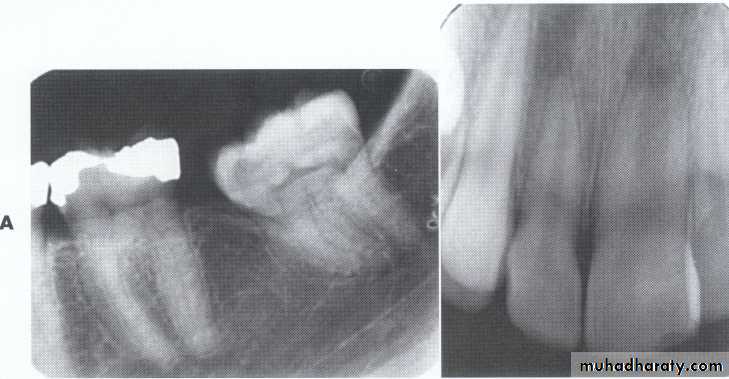

Dilaceration of the crown

specimenX-Ray

Dilacerated root. The apical portion of the root is bent buccally or lingually into the plane of the central ray. Note the halo in the apical region, produced by the PDL

space (arrow).